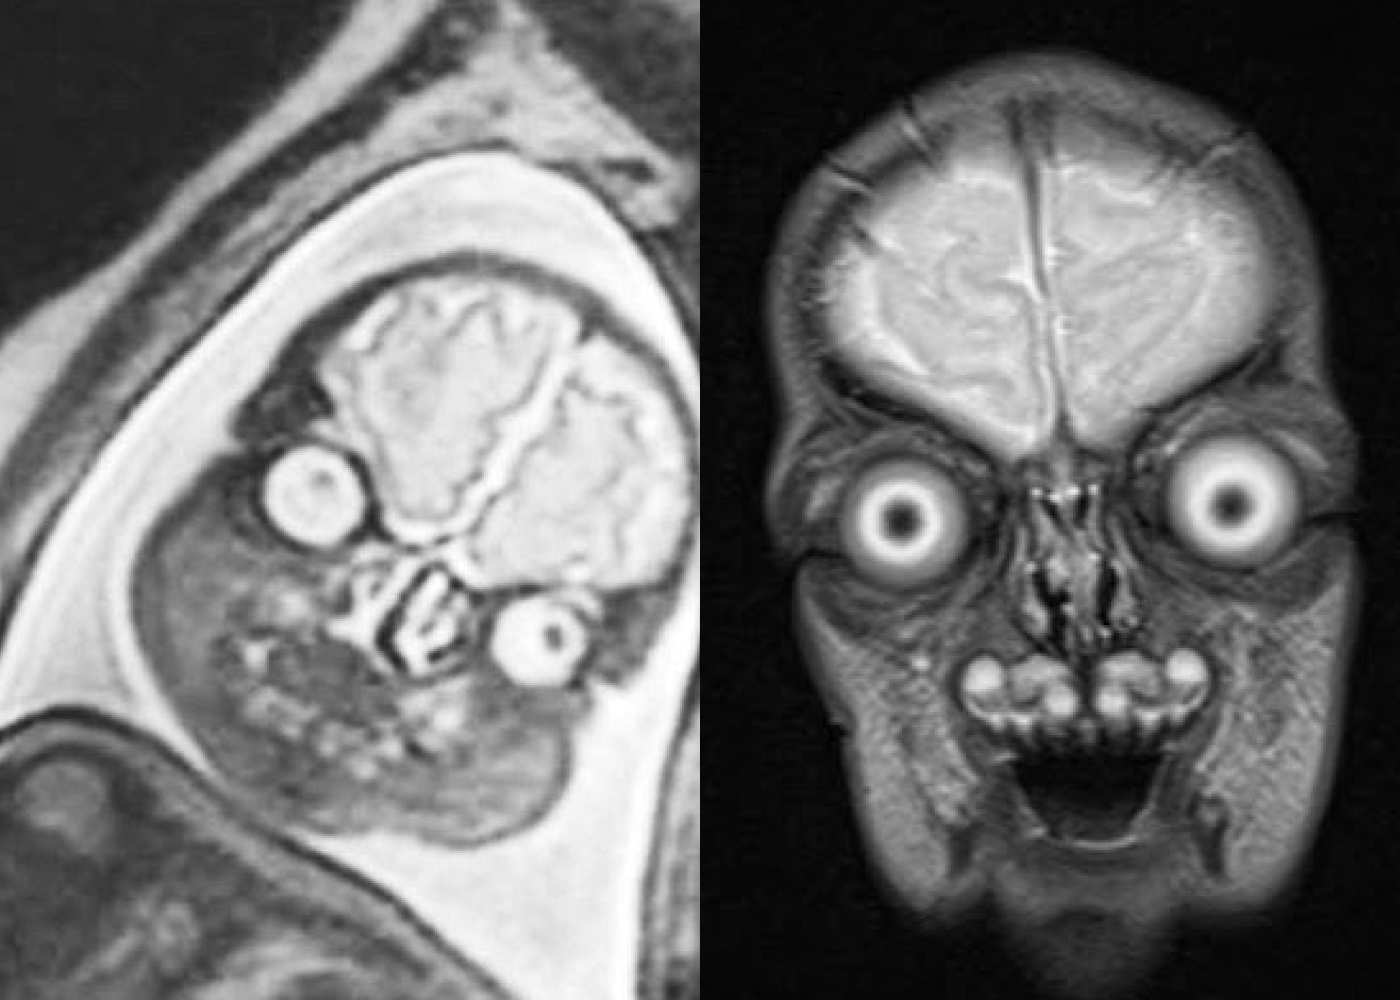

МРТ головного мозга: показания и результаты

Раздел: Визуальный дайджест